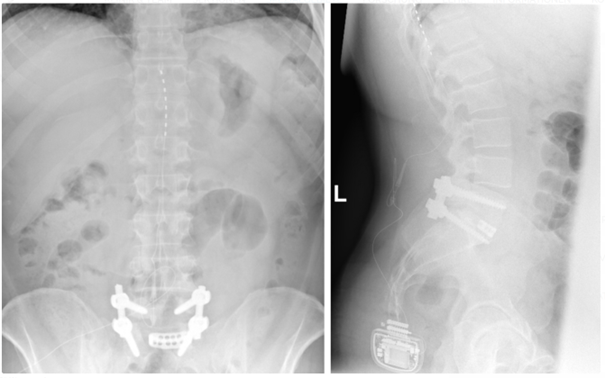

Bei der Rückenmarkstimulation wird in der Wirbelsäule eine Elektrode platziert. Über diese werden elektrische Impulse an das Rückenmark abgegeben. Die Elektrode ist mit einem Impulsgeber (vergleichbar mit einem Herzschrittmacher) verbunden. Das operative Verfahren gliedert sich in zwei Abschnitte: Im ersten Eingriff erfolgt, unter örtlicher Betäubung und Röntgenkontrolle, die Platzierung der Elektrode im Rückenmarkskanal. Im Anschluss erfolgt eine Testphase. Ziel ist es, die Abdeckung des Schmerzareals durch die Stimulation und die daraus resultierende Schmerzreduktion zu testen. Bei zufriedenstellendem Ergebnis wird in einem zweiten Eingriff der Impulsgeber unter die Haut implantiert.

Die über die Elektrode abgegebenen Impulse bewirken im Bereich des Rückenmarks eine Unterbrechung/Verminderung der Schmerzleitung der Nerven. Hierbei ist es notwendig, bei jedem Patienten individuell die notwendigen Stimulationsparameter festzulegen. Die schmerzreduzierende Wirkung der Neurostimulation kann in einem zweiten Schritt die Verringerung der Schmerzmedikation nach sich ziehen.

Röntgenbild zur Rückenmarkstimulation